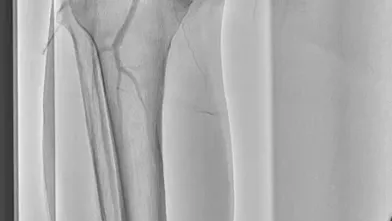

過去にSFAに留置された総長約35 cmの3本のBMSの入口部からの閉塞(動画1)近位端はSFA入口部から1 cm程度の健常部があり、遠位端は膝窩動脈近位部(P1)で側副血行流入部まで1 cmの余白がある。対側山越えアプローチで6 Frガイディングシースを挿入して治療を開始した。ステント外を通過しないように0.035 inchのガイドワイヤーを選択すると容易に遠位部へ到達することが出来た(動画2)。この手ごたえから血栓性病変であることが予想された。持続吸引カテーテルを用いて何度か血栓吸引を行ったが血流は再開しなかった(動画3)。

血管内超音波(IVUS)を行うとガイドワイヤーはステントの中心部を通過していたが、予想通り病変内には大量の血栓が堆積していた(動画4)。7 mmのバルーンで拡張したのち、ステント遠位端より2 cm程度離れた遠位の健常部にhealthy landingをとって(動画5)バイアバーン® ステントグラフト6 × 250 mmを留置した。近位側はステント近位端より1 cm程度離れたSFA入口部の健常部にhealthy landingをとって(動画6)バイアバーン® ステントグラフト7 × 150 mmを留置した。上下端とも既存のステントより外側にランディングをとること、ステントグラフトの電子添文の「使用上の注意」にあたる主要な側枝に注意して、大腿深動脈(DFA)や側副血行の流入部にかからないよう留意した。後拡張は血栓の上下方向へのprotrusionを防ぐ目的で先に遠位端、近位端の順に高圧バルーンで拡張し健常部血管壁への圧着をとった。ステントグラフトの中間部への後拡張はそのあとに続いて行った。最終造影で末梢まで塞栓がないことを確認して終了した(動画7)。